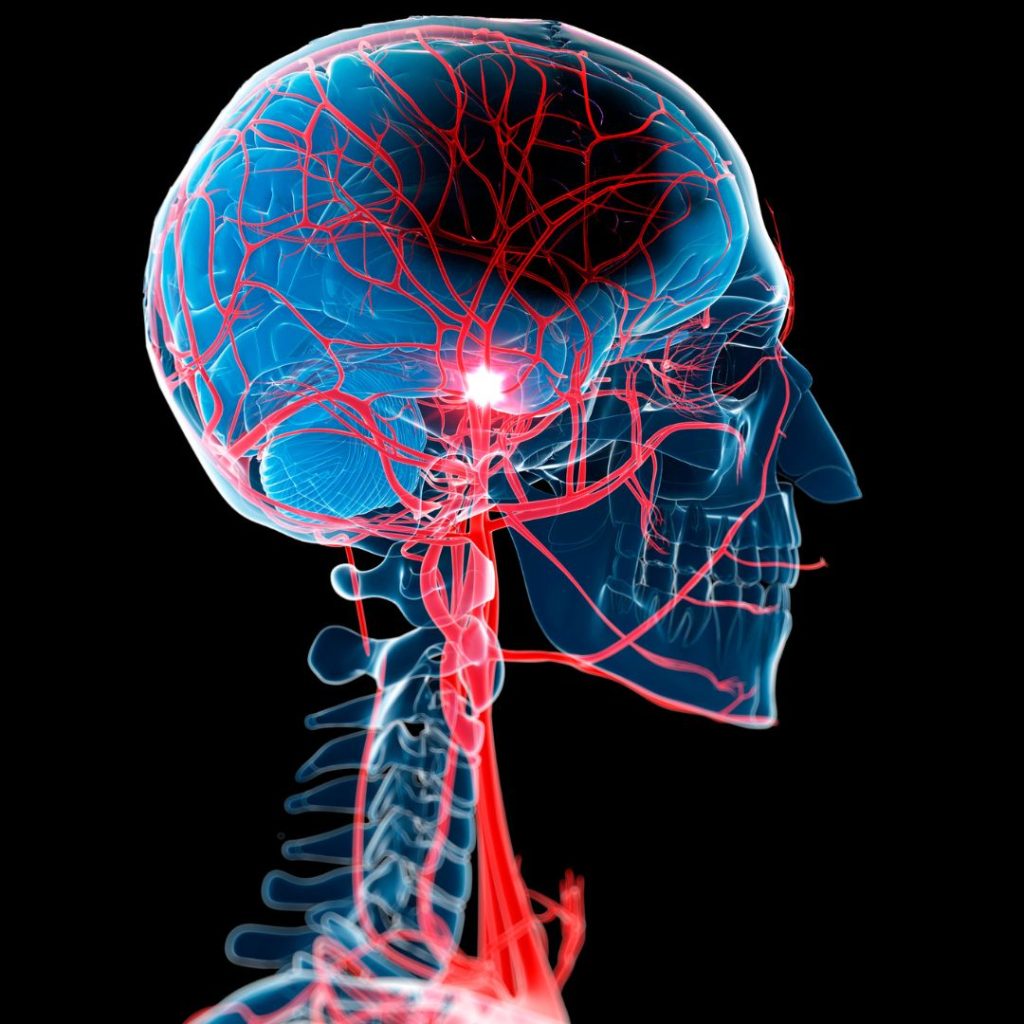

Die Bezugstherapie bezieht sich auf eine individualisierte, koordinierte und oft intensivierte Rehabilitation, die eng auf die spezifischen Bedürfnisse und Ziele des Patienten zugeschnitten ist, oft unter Einbeziehung neuer Technologien wie der transkraniellen Magnetstimulation (TMS) oder Robotik, um die Neuroplastizität zu fördern, die gesunde Seite einzuschränken (Forced Use) und eine ganzheitliche Wiederherstellung von Funktion, Sprache und Kognition zu erreichen, indem alle Therapeuten (Physio-, Ergo-, Logopädie) zusammenarbeiten.

- TMS (Transkranielle Magnetstimulation): Stimuliert Nervenzellen im Gehirn, um die Reorganisation und Wiedererlernung von Funktionen zu fördern.